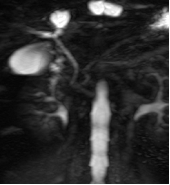

1.4 磁共振成像MRI

1946年美国Stanford大学 Felix Bloch和Harvard大学的 Edward Purcell各自独立行磁共振现象研究,1952年他们荣获诺贝尔物理学奖。MRI应用逐渐扩展,在医学诊断中被认为是最重要的进展。

MR是一种生物磁自旋成像技术,它是利用原子核自旋运动的特点,在外加磁场内,经射频脉冲激后产生信号,用探测器检测并输入计算机,经过计算机处理转换后在屏幕上显示图像。